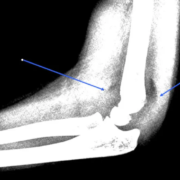

Det var derfor enormt praktisk, at jeg selv kunne vise det billede, jeg tog af lægens skærm, og at jeg i min artikel om kontrollen af skulderskaden havde indsat data fra SP. Der vil sikkert være mange patienter, der ikke møder frem i fysioterapien med røntgenbilleder og lægens notater fra hospitalet. Faktisk vil jeg tro, at jeg tilhører mindretallet.